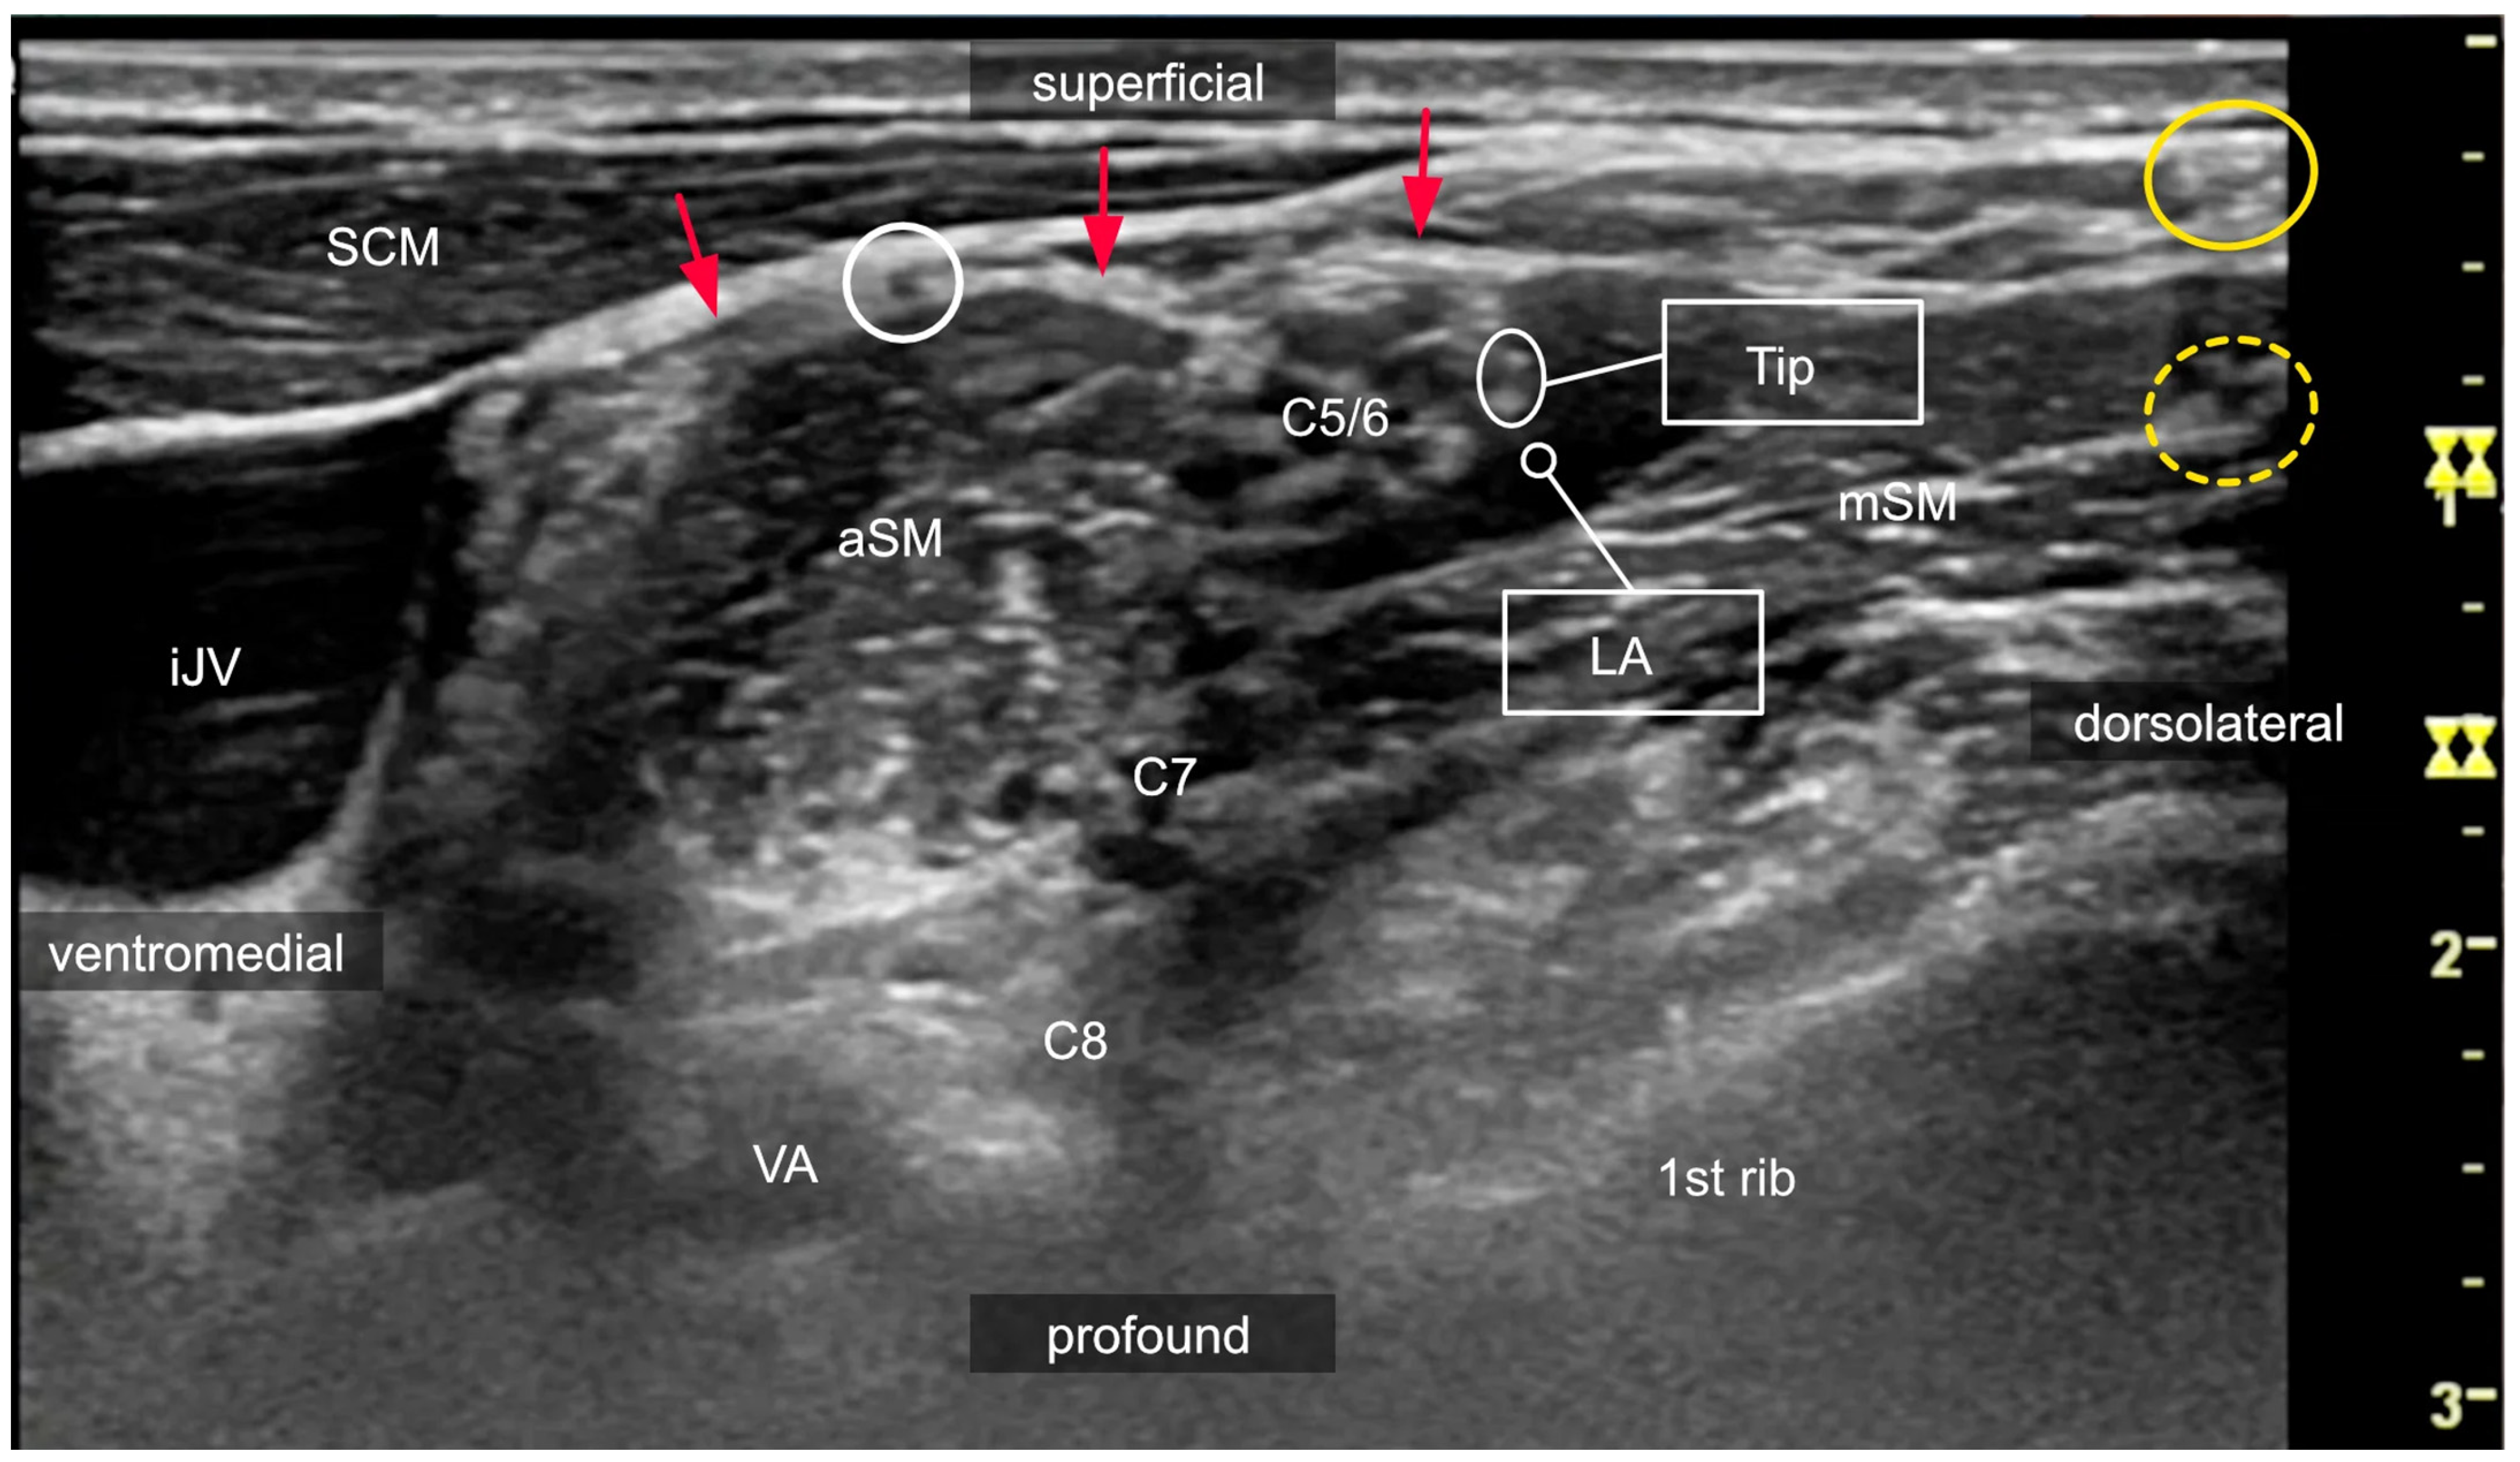

3.2. Interscalene Access

3.3. The Risks of Interscalene Catheters

3.6. The Role of Ultrasound